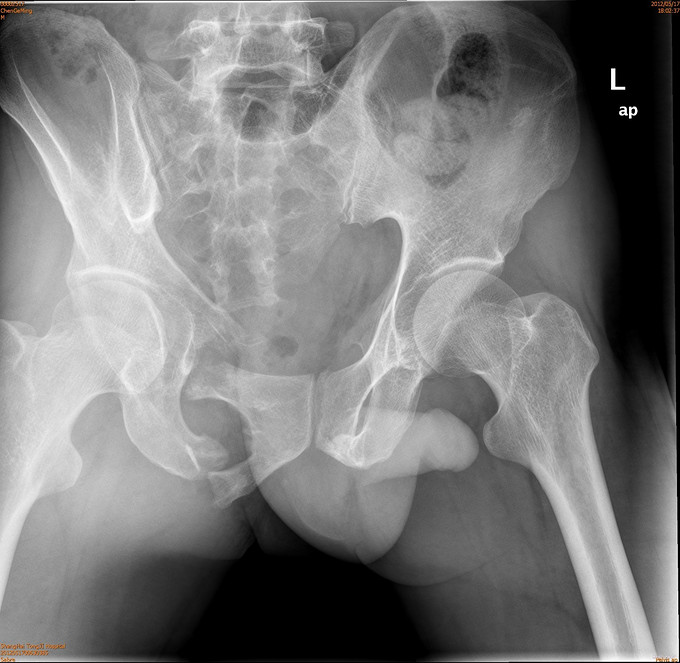

患者男,41岁,因车祸致双侧髂腰部、中下腹部及会阴部疼痛,伴尿道出血1小时。患者于1小时前不慎被汽车撞伤,当即感到双侧髂腰部、中下腹部及会阴部剧痛,尿道口有鲜血渗出,有昏迷,后自行苏醒,120送入我院急诊,CT示两侧骶髂关节前缘骨折,双侧耻骨上下支骨折,周围血肿形成。急诊导尿失败,遂入院治疗。

诊断为耻骨上下支骨折,兄弟科室会诊治疗结束后,患者病情稳定,行切开复位内固定术。